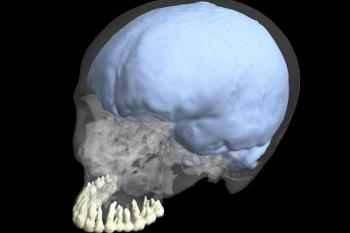

跟其他癌症一样,它们是因为控制细胞成长的讯息发生了错误而导致畸胎瘤。畸胎瘤同时也会发挥像干细胞一样的功能。在这个特殊的例子中,这名日本女孩卵巢内尚未成熟的卵,并没有接受到按兵不动的指令,于是不只是女孩的卵开始分裂,这些新的细胞形成了毛发以及一层细骨头,包覆着一个类似有脑干以及小脑的脑类结构。

畸胎瘤虽然鲜少会夺命,但是神经细胞类的肿瘤却有一种特殊的风险。免疫系统将癌症视为一种威胁,所以会误把病患本身的脑细胞视为敌人。还好这名病患的免疫系统并未攻击自身的神经系统。在畸胎瘤内发现神经细胞或许没有那么罕见,但是这些细胞却自我形成神经结构则是十分罕见,尤其是这些组织可能会传递神经脉冲。

新南威尔斯大学的雷普萨门医师在接受《新科学家》的访问时提到“:一般来说,在卵巢畸胎瘤内发现神经细胞还蛮常见的,但是类似成人脑部的结构却很罕见。”

脑干在发育完全的情况下,负责维持个体生命,而小脑则是控制我们行动的关键。毫无疑问的,这名青少女体内的细胞群,离能够思考以及感觉外在的生物体还很远。